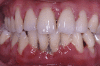

Periodontitis is a common chronic inflammatory disease characterised by destruction of the supporting structures of the teeth (the periodontal ligament and alveolar bone). It is highly prevalent (severe periodontitis affects 10-15% of adults) and has multiple negative impacts on quality of life. Epidemiological data confirm that diabetes is a major risk factor for periodontitis; susceptibility to periodontitis is increased by approximately threefold in people with diabetes. There is a clear relationship between degree of hyperglycaemia and severity of periodontitis. The mechanisms that underpin the links between these two conditions are not completely understood, but involve aspects of immune functioning, neutrophil activity, and cytokine biology. There is emerging evidence to support the existence of a two-way relationship between diabetes and periodontitis, with diabetes increasing the risk for periodontitis, and periodontal inflammation negatively affecting glycaemic control. Incidences of macroalbuminuria and end-stage renal disease are increased twofold and threefold, respectively, in diabetic individuals who also have severe periodontitis compared to diabetic individuals without severe periodontitis. Furthermore, the risk of cardiorenal mortality (ischaemic heart disease and diabetic nephropathy combined) is three times higher in diabetic people with severe periodontitis than in diabetic people without severe periodontitis. Treatment of periodontitis is associated with HbA(1c) reductions of approximately 0.4%. Oral and periodontal health should be promoted as integral components of diabetes management.